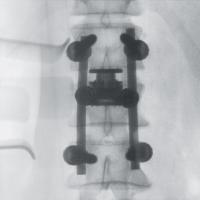

手術室内で移動式のX線装置を使用して行う撮影です。

直接目視できない部分をX線画像でリアルタイムに見られるため、より安全に手術を行うサポートができます。

一例として、金属のボルトを骨内に挿入する際に、位置や角度、深さを様々な方向から観察できるほか、装置を回転させて撮影することで、CT画像のような自由な断面像を得ることも可能です。

- 手術手技に必要となる三次元画像情報を、リアルタイムかつ的確に提供します。

高精細なフラットパネルディテクタを搭載しており、従来よりも広い視野でゆがみのない鮮明な画像が得られます。